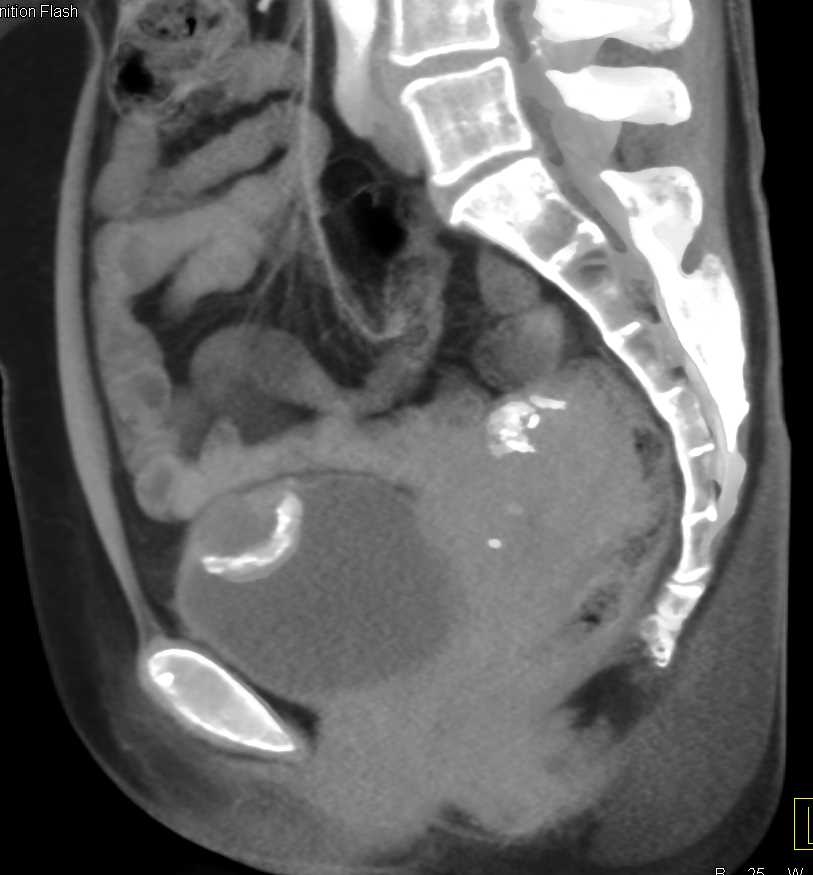

Urachal Carcinoma of the Bladder